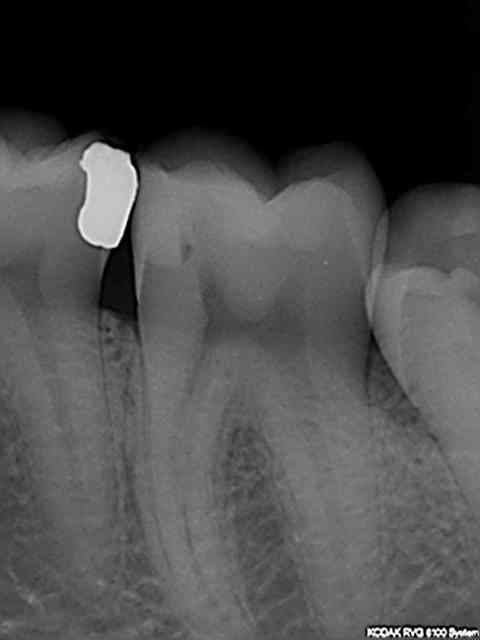

Sinon une fois en place la métafix est une tuerie, gaffe à ne pas faire le mur trop épais car si l'espace est trop étroit entre le mur et la paroi proximale de la cavité le compo a du mal à fuser ( voir la 37) lors de son foulage (a moins d'utiliser du sdr fluide par exemple.

R34 g7agre - Eugenol

R36 mldzgm - Eugenol